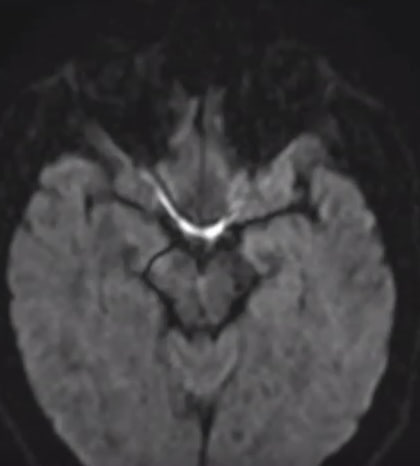

>>1624717 (OP)

>>1613491 →-аноним на связи.

Сходил в центр РС, снова на МРТ (прошло почти 4 месяца).

Диагноз, не знаю, к счастью ли, пока что G37.9...

Все еще надеюсь, что это что-то менее неприятное, чем рассеянный склероз.

Был сегодня на МРТ, с марта динамики нет.

По самочувствию - в какой-то момент почувствовал себя почти здоровым, начал снова строить планы на жизнь.

На прошлой неделе начался небольшой тремор рук, визуальный заметный только если держать их на весу вытянутыми. Прошел.

С понедельника чувствую периодически легкую головную боль, сонливость, упадок сил, ощущение воспаленности (как при температуре при ОРВИ, например). С одной стороны нет сил на лишние движения, с другой - движение отвлекает от неприятных ощущений.

И такое колеблющееся самочувствие стало регулярным.

На фоне ухудшения самочувствия появились трудности с мотивацией, каждое действие приходится чем-то оправдывать, кажется ухудшилась способность к концентрации, начинаю впадать в отчаяние, заниматься самокопанием, искать в прошлом причины этого недуга.

По анализу крови из нормы выбиваются только лимфоциты и лейкоциты (пик-2).

Опытным анонимам вопрос, что хуже/опаснее всего в моем заключении МРТ?